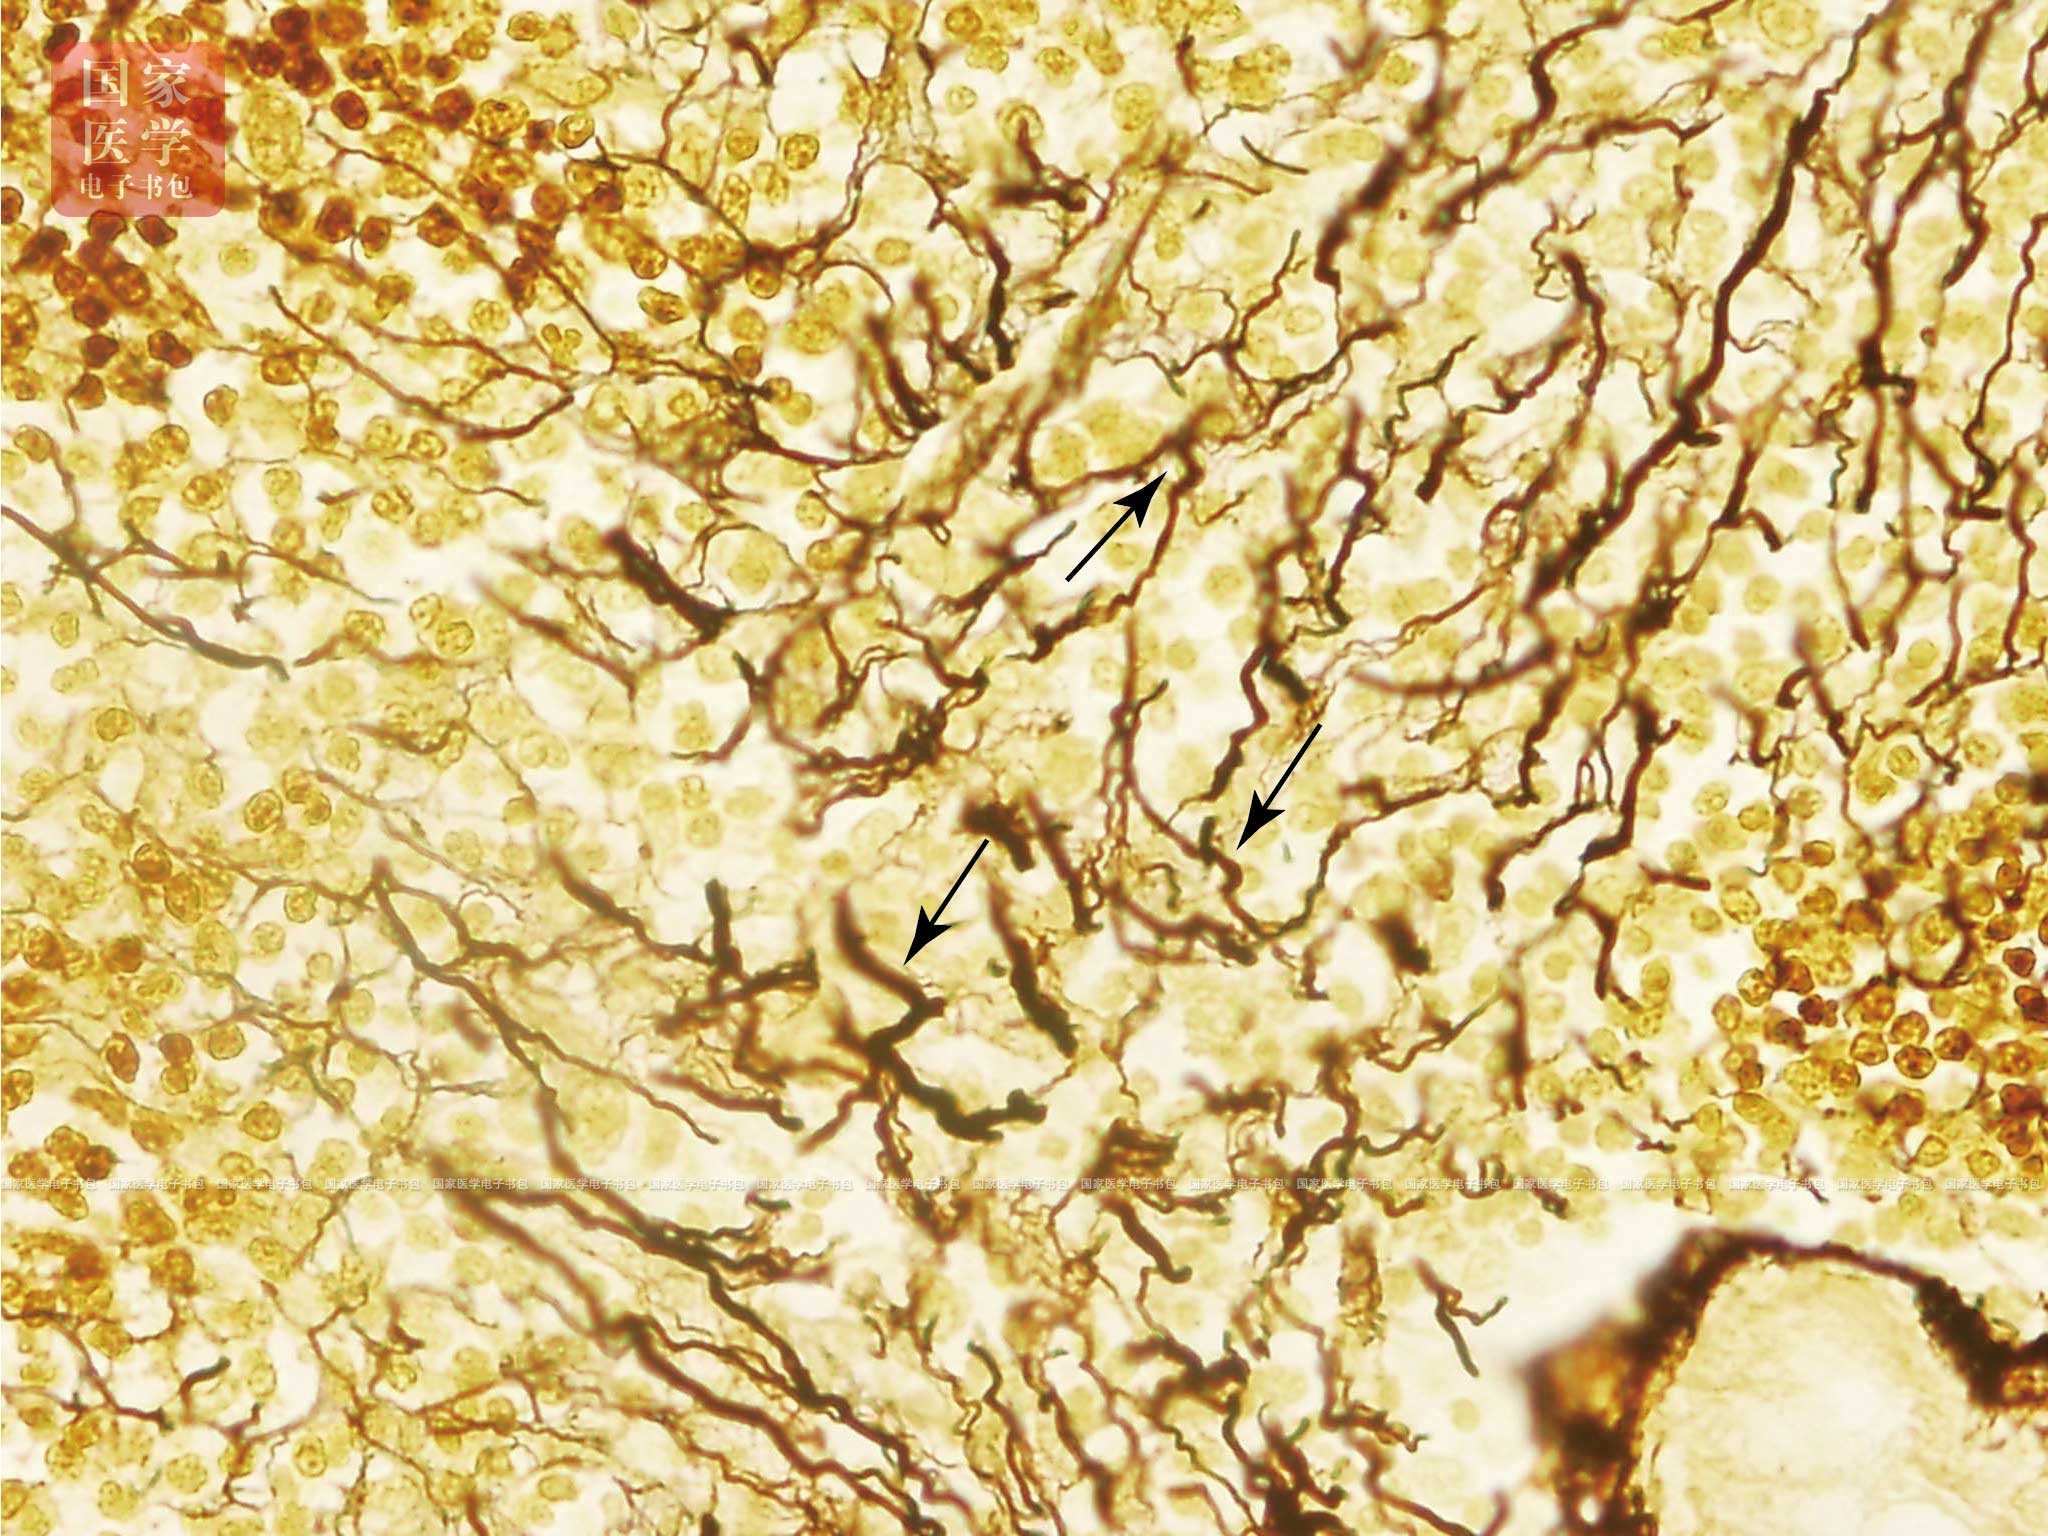

网状组织(reticular tissue)由网状细胞(reticular cell)与网状纤维构成网状支架(视频3-4-1),网孔中由大量造血细胞或淋巴细胞所形成。是造血器官和淋巴器官的基本组织成分。网状细胞有突起,呈星状,是特殊类型的成纤维细胞,相邻细胞的突起相互连接成网(图3-8-4),胞核较大,圆形或卵圆形,着色浅,常可见1~2个核仁,胞质丰富,粗面内质网较发达。网状纤维由网状细胞产生,he染色不能显示,银染成黑色,分支交错,连接成网(图3-8-5),为淋巴细胞发育和血细胞发生与发育提供适宜的微环境(microenvironment)。

视频3-4-1 网状组织 图3-8-4 网状细胞光镜图(he染色,高倍) 图3-8-5 网状纤维银染